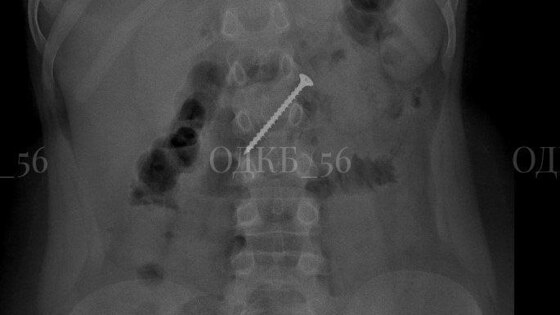

Проглотил пятисантиметровый саморез: оренбургские врачи спасли ребенка

Специалисты Областной детской клинической больницы вытащили из кишечника ребенка саморез. Своевременное вмешательство профессионалов спасло юному пациенту жизнь.

Девятилетний мальчик попал в больницу после того, как родители заметили тревожные симптомы. После обследования врачи обнаружили инородное тело в желудке ребёнка.

Специалисты оперативно провели операцию под общим наркозом и извлекли опасный предмет из кишечника пациента, избежав серьезных последствий, включая риск непроходимости и прободения стенки органа.